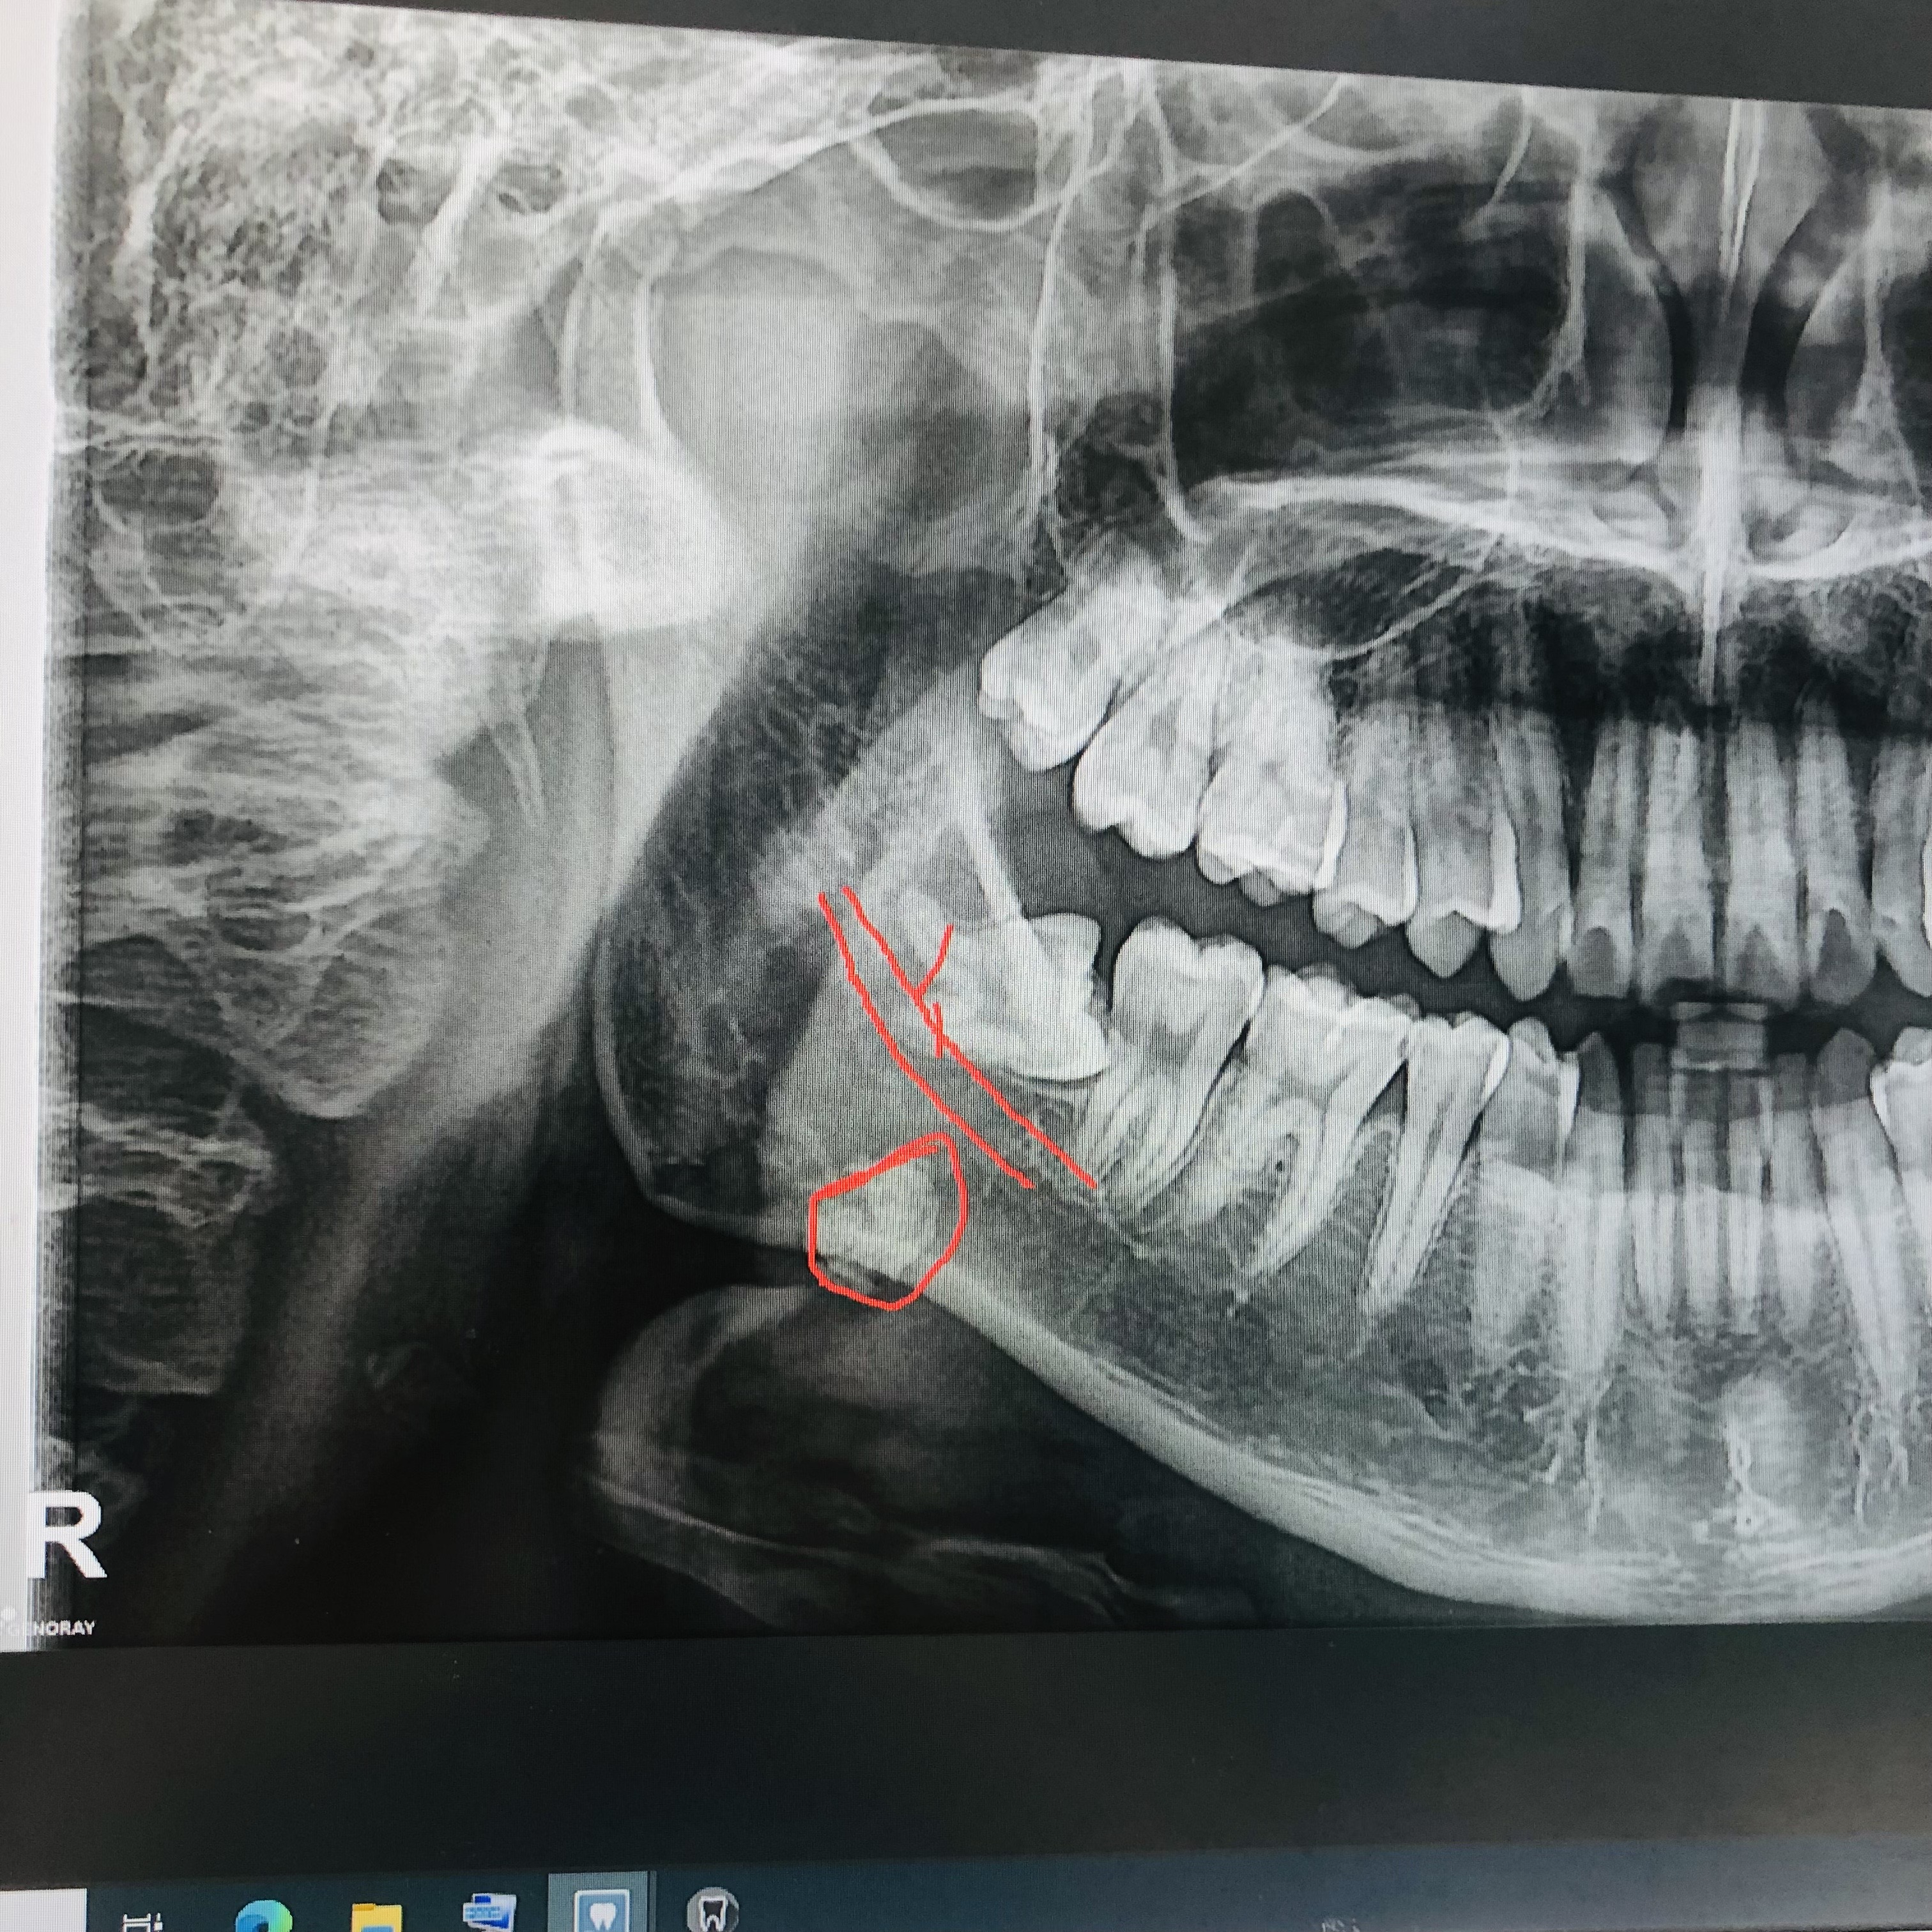

타석증 발견

사랑니 4개를 다 빼느라 치과에서 CT를 찍었는데 치과의사쌤이 타석증(침샘결석)이 의심된다면서 이비인후과를 가보라고 하셨습니다.

사랑니 발치의 고통을 머금고 동네 이비인후과에서 타석증 판정받고 대학병원에 제출할 소견서를 받았습니다..

대학병원에서도 의사선생님이 혀밑에 손가락을 넣어서 만져보시고 있는것 같다고 CT도 찍고나서 타석증 판정 제대로 받았습니다.